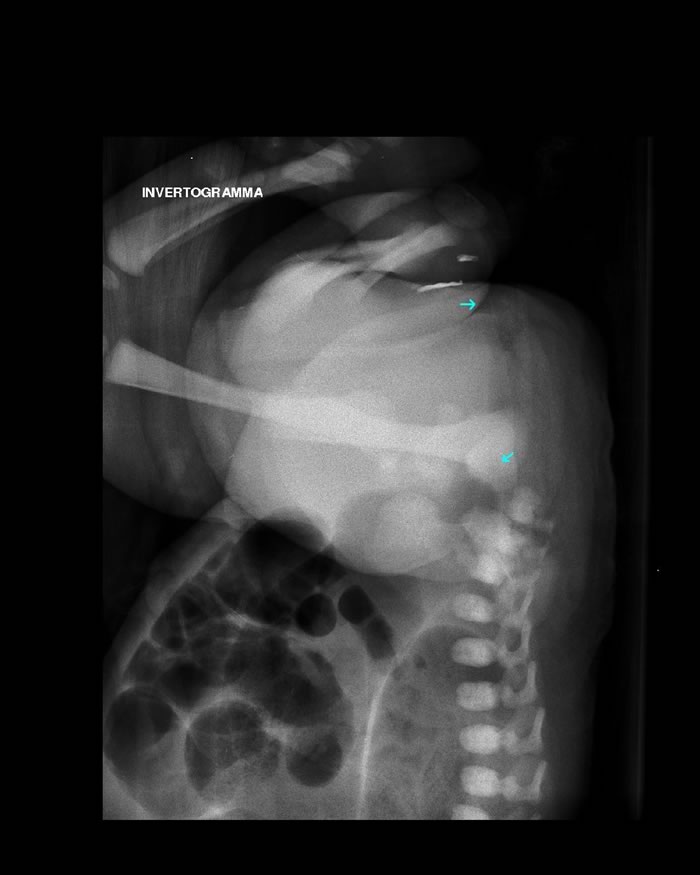

- invertogramma (fig.3), che dimostra una distanza di circa 2 cm tra il cul di sacco del retto, disegnato dall'aria, e la sede dell'orifizio anale.